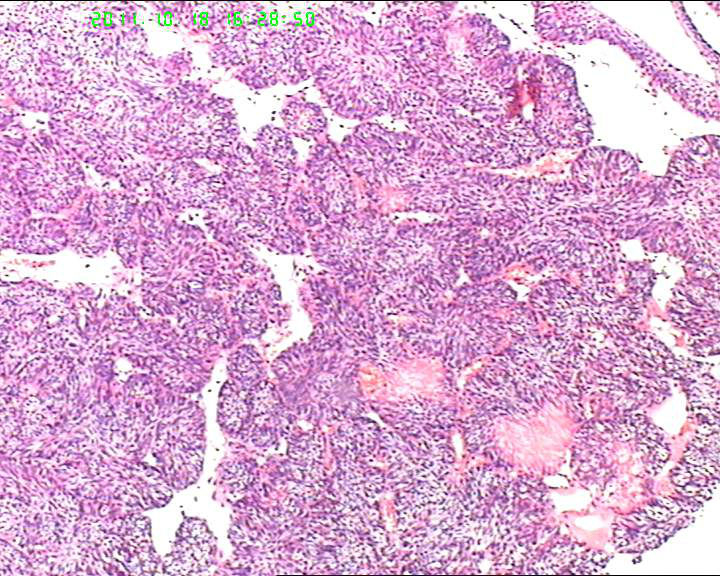

70岁女性体检发现膀胱肿物,是癌吗?

膀胱后壁一2*1cm大小肿物